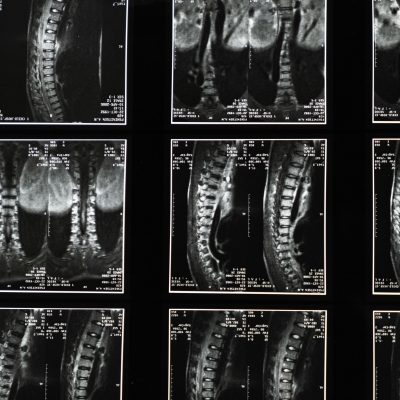

All About Neck and Back Injuries Caused by Car Accidents

Major Florida car accidents can result in severe injuries, many of which involve the neck and back. Some neck and back injuries involve temporary symptoms that go away with time while others can last for life. The most severe neck and back injuries can result in life-changing disabilities. If your...